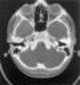

Congenital absence of neural arch